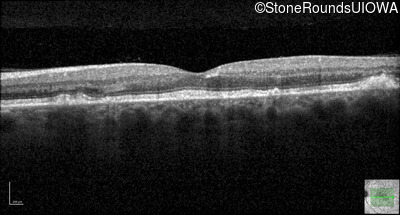

Optical Coherence Tomography - Right - 20/20 -1 sc

Exemplar / OCT Stack